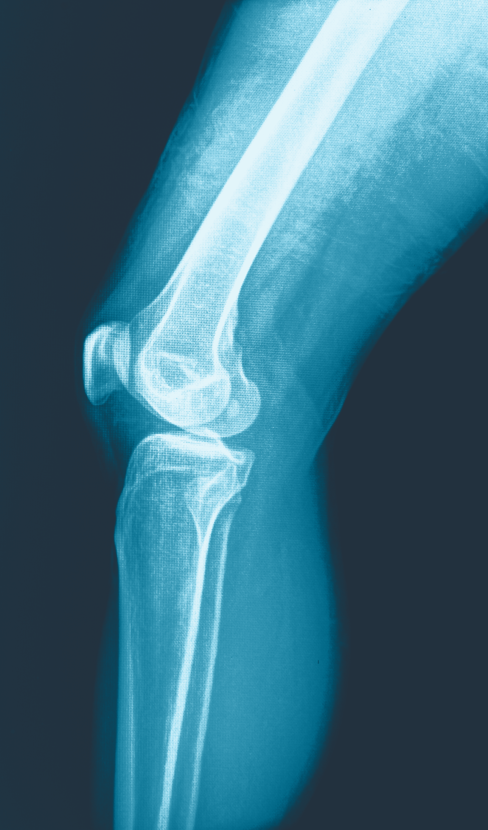

Knæalloplastik er betegnelsen for indsættelse af et kunstigt knæled. Primær indikerer, at det er den første operation med indsættelse af en alloplastik.

Det operative indgreb foretages primært på grund af slidgigt i knæleddet.

Formålet med indgrebet er smertereduktion og forbedring af funktionsniveauet (1).